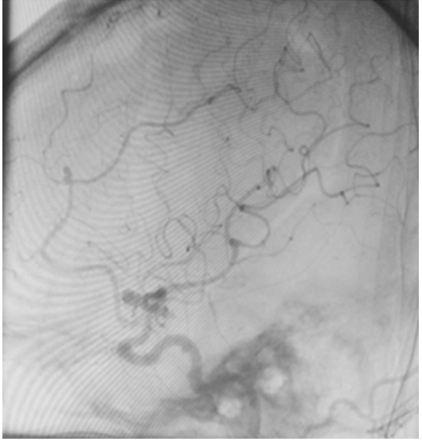

Uma paciente de 66 anos de idade, tabagista, hipertensa com tratamento irregular. Apresentou cefaleia súbita de severa intensidade associada a náuseas. Ao exame físico, observaramse AC = RR2T com BNF, FC = 100 bpm, AP = MVF sem RA, FR = 15 irpm, PA = 182 mmHg x 100 mmHg, SatO2 em ar ambiente = 97%, Glasgow 15, pupilas isofotorreagentes, sem deficits focais. TC crânio e arteriografia a seguir.

Fonte: Acervo pessoal.

Acerca desse caso clínico e com base nos conhecimentos médicos correlatos, julgue os itens a seguir.

Segundo a classificação da World Federation of Neurological Societies (WFNS), a paciente seria classificada como grau 1.